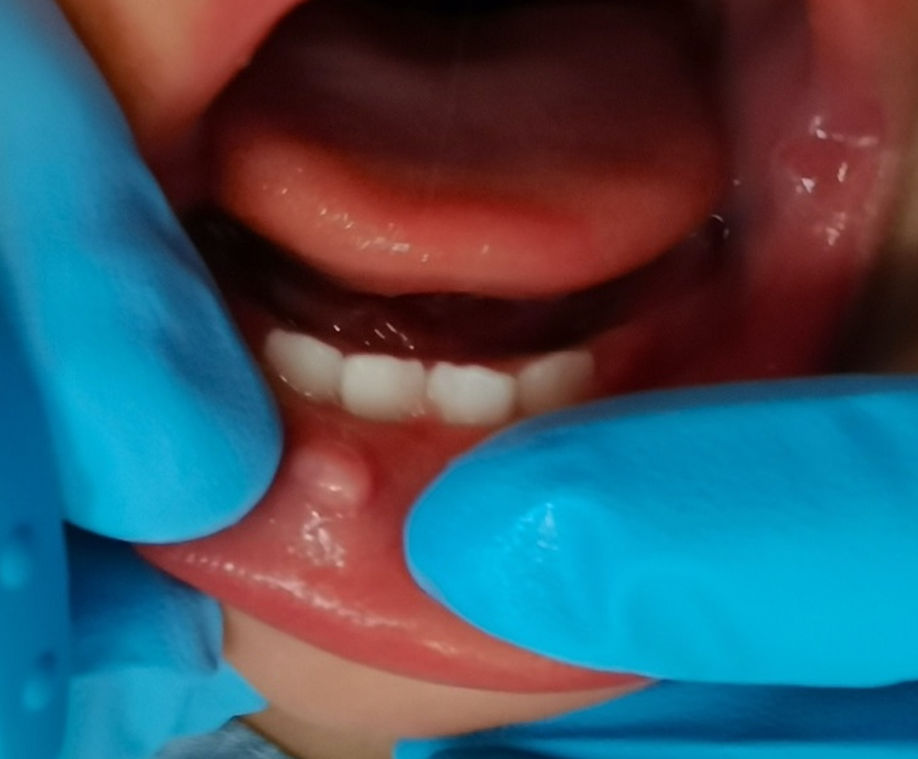

A 5-year-old girl with a small brown area at the gumline.